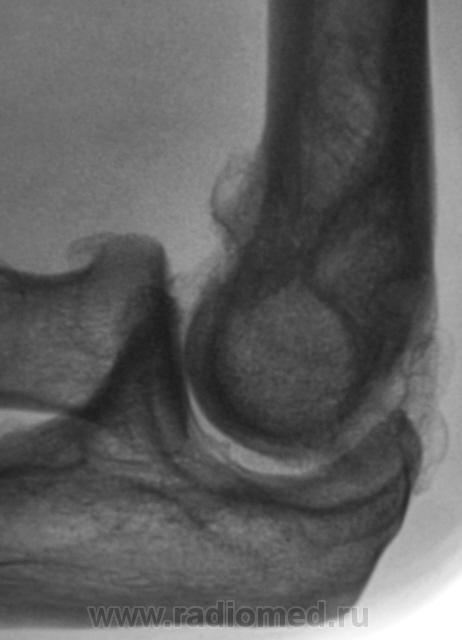

Пациент направлен на рентгенографию локтевого сустава. Была травма или не была не помнит. Пациент весьма пьющий, направлен хирургом с диагнозом "перелом". Рука в локтевом суставе полность не разгибается.

Ваше мнение уважаемые коллеги?

Наверно, застарелый перелом в области блока плечевой кости. Не понятен периостит.